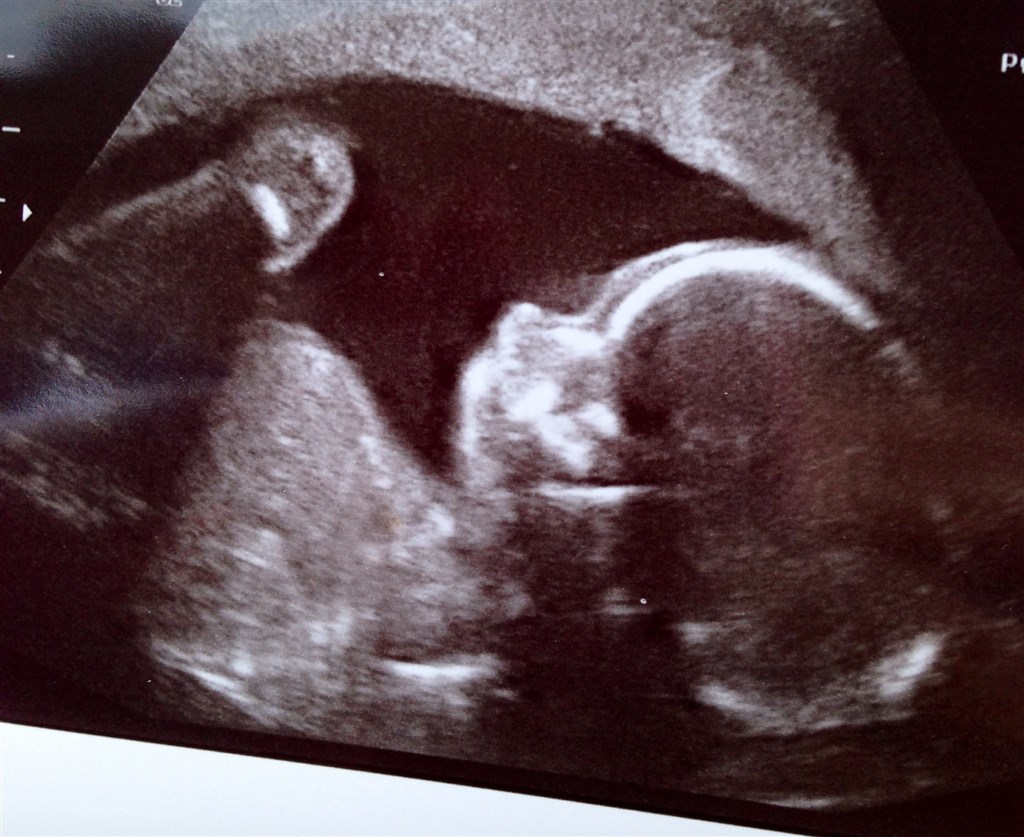

Så har vi i dag været inde og se vores guldklump, og alt så perfekt ud! Det er en rigtig aktiv lille baby der ligger inde i sin hule, og jeg mærker den hver dag!

Det bliver spændende om det er en lille gut eller gutinde der gemmer sig derinde, så nu kan tiden kun gå for langsomt!